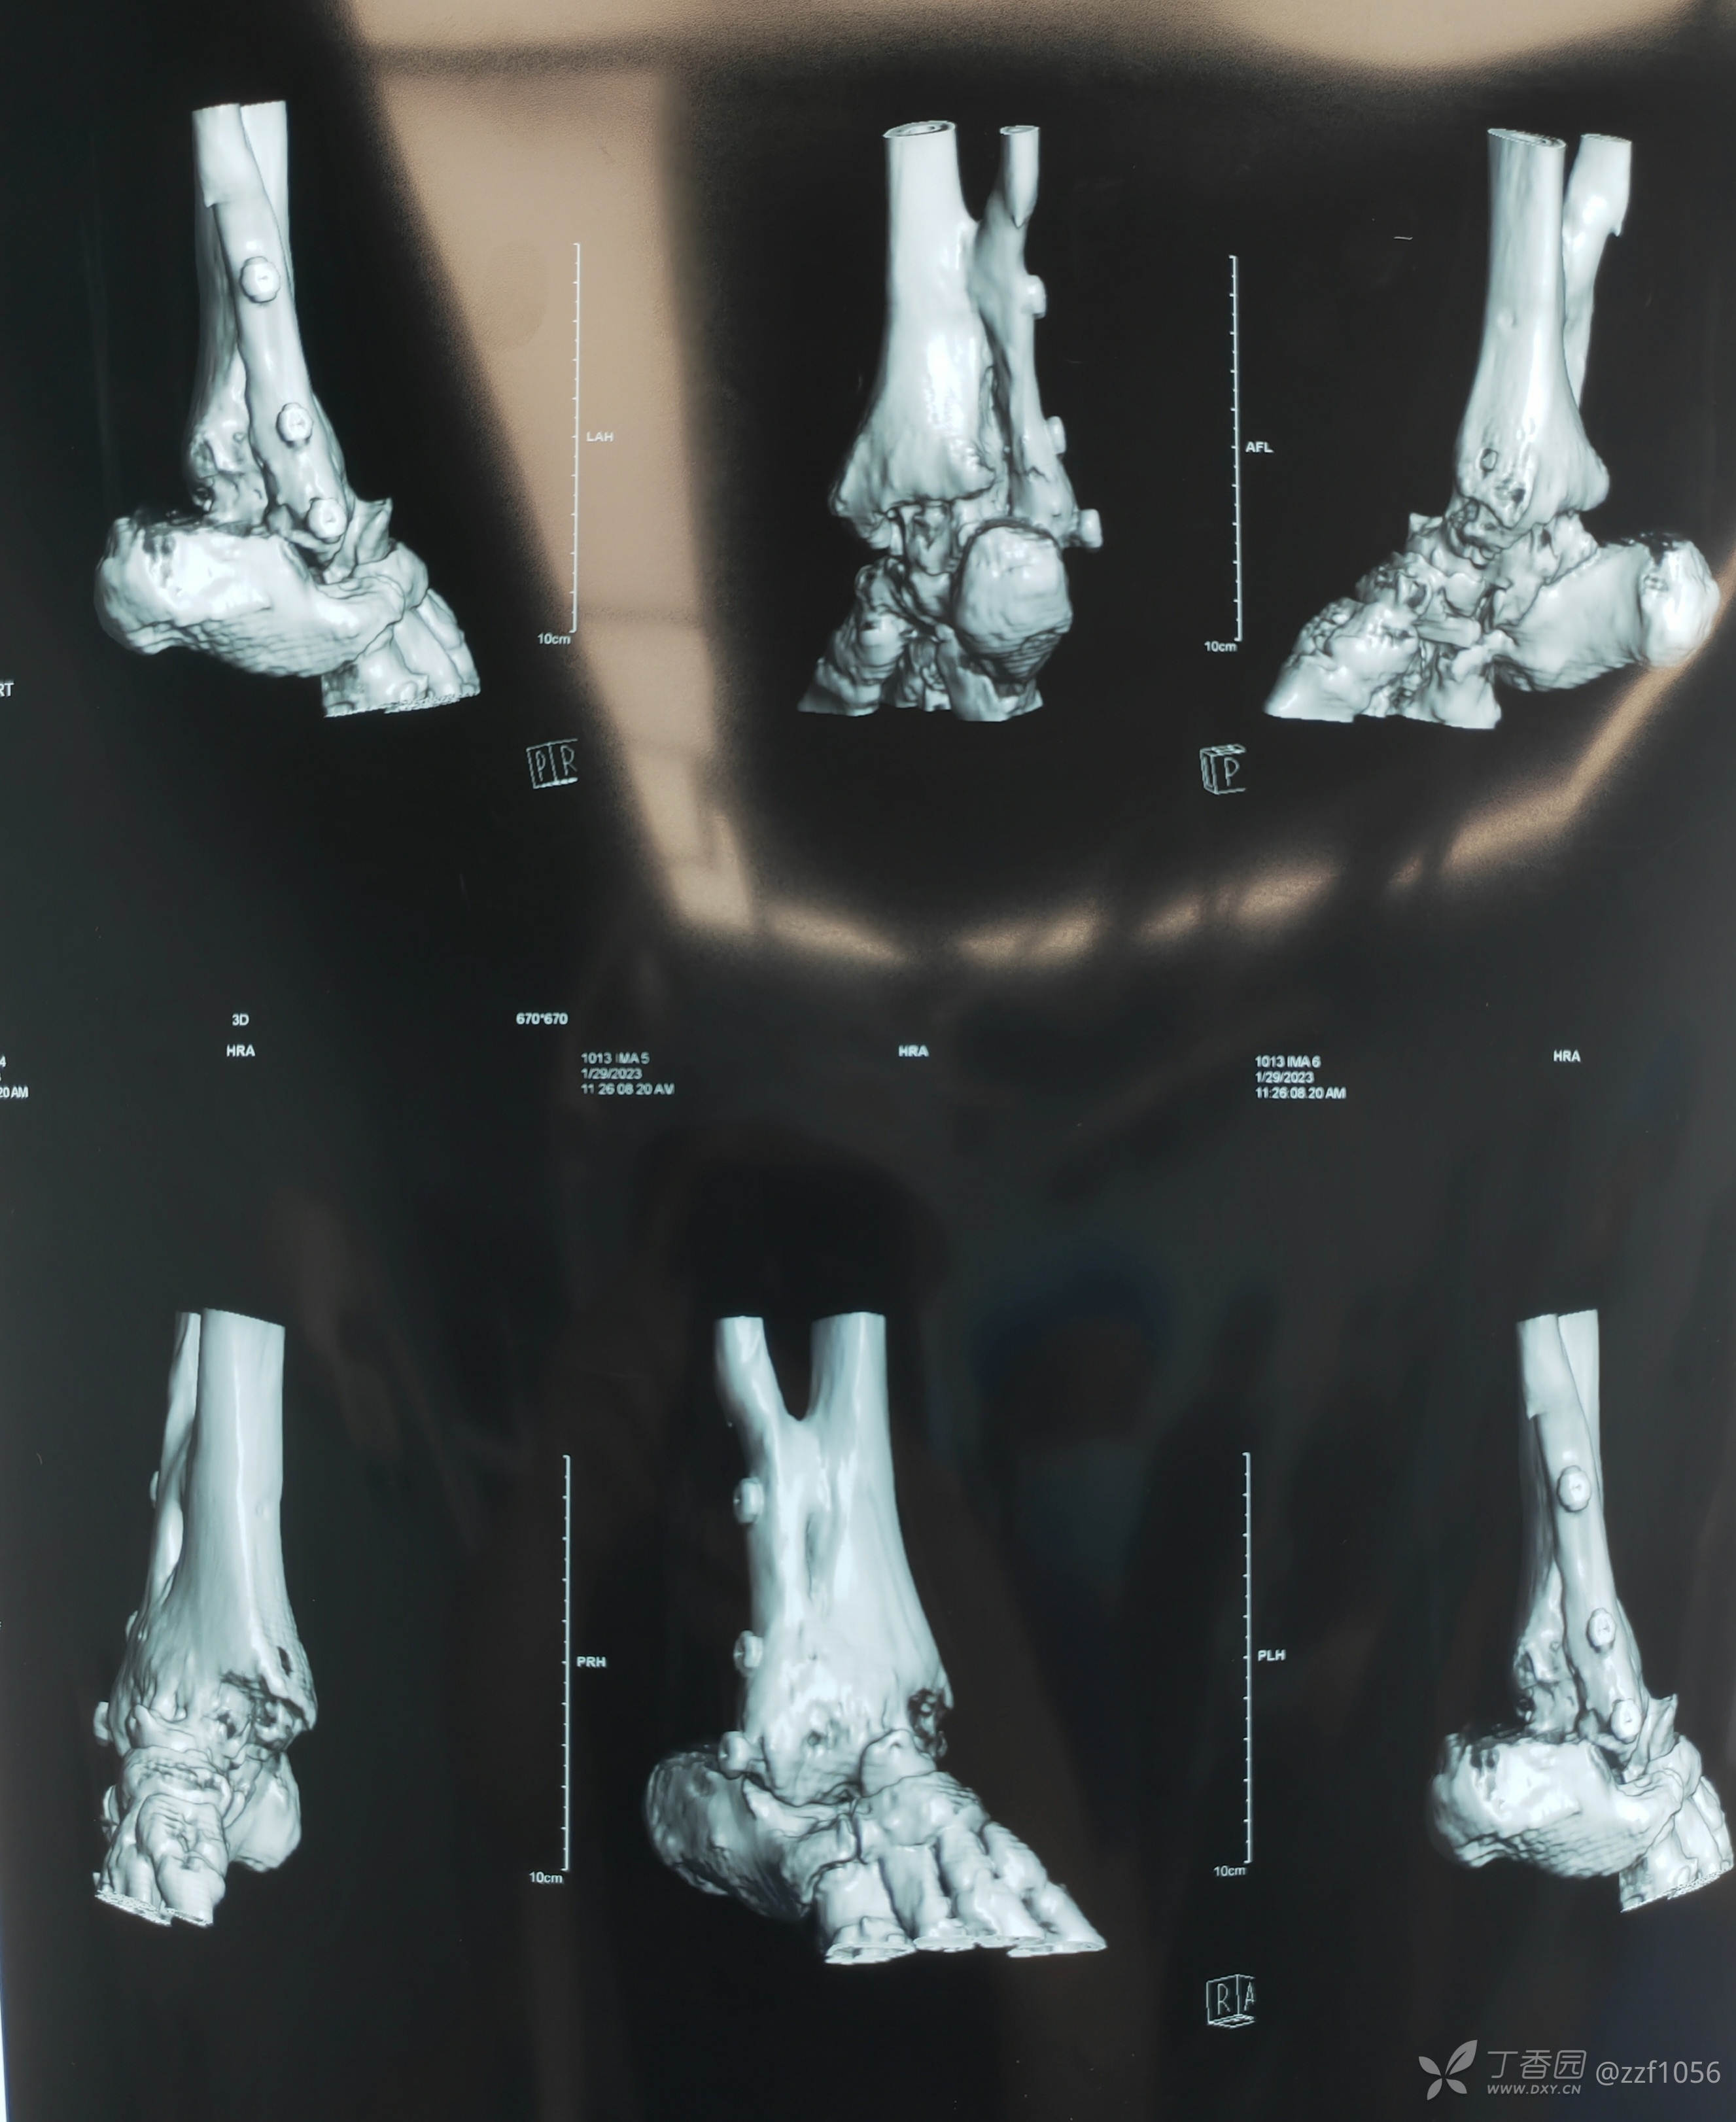

看一下目前CT

从骨折畸形愈合形态应该能推测当时接近于劈木机损伤,旋前外旋四度骨折。

就备了一块融合钢板,偏长了点

应该是90°➕

总体满意